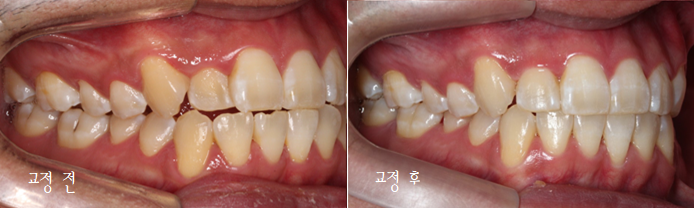

이번에는 덧니 고민으로 오신 환자분인데요.

윗니 오른쪽 두 번째 앞니가 들어가 있고,

다른 앞니끼리도 너무

세게 닿아서 고민이라고 오셨어요.

사진을 보실 땐

눈에 보이는 방향의 왼쪽이

환자에게는 오른쪽입니다.

전후 사진 먼저 볼까요?

짠~

첫 방문 때 이렇게 아래 앞니도 깨져있고,

#12 치아는 안으로 들어가 있었습니다.

환자분은 #13 이 튀어나왔다고 생각하시던데,

이렇게 씹는 면 사진으로 보면

#13이 튀어나왔다라기보단

#12가 상대적으로 들어가 있는 게 맞죠.

배열이 처음보다 훨씬 좋아졌습니다.

차이가 조금 더 느껴지실까요 ?^^

마찬가지로 좌 before, 우 after입니다.

이렇게 보면 훨씬 개선된 것이 눈에 띄시죠?^^